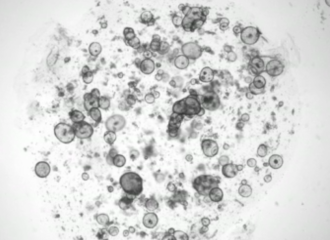

图片来源于研究论文

为了克服这一障碍,研究人员采用先前用于其他器官的方法,构建了来源于成体干细胞的小鼠和人类泪腺3D类器官。类器官可以持续生长数月,并能够重现分泌大部分泪液的泪腺上皮组织在结构、转录和功能方面的特征。值得注意的是,如果暴露在能刺激泪液分泌的神经递质——去甲肾上腺素中,这些类器官也会像气球一样膨胀起来。